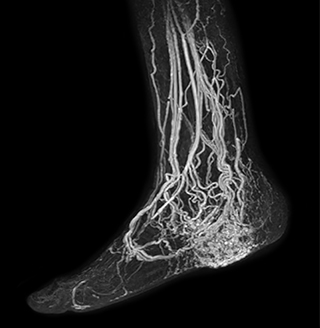

Another example is the foot examination for diabetic patients, which has improved dramatically. “The forefoot is generally difficult to image with MRI because of the inhomogeneities that the toes create – it’s hard to obtain good fat saturation in that area. Here, mDIXON made a huge difference right away, we obtain much better image quality,” Dr. Peña says. “Using mDIXON, Compressed SENSE and the dS FootAnkle coil, we have been able to reduce the scan time, so that we can now also include an additional 3D STIR sequence to visualize both arteries and veins in the foot.”

Avila adds: “In addition, since most of these patients are in a significant amount of pain, it’s important to perform the examination as quickly as possible. With Compressed SENSE and mDIXON we have been able to reduce the scan time from about 45 minutes to just 15 minutes. Not only does this improve patient comfort, we see that it also helps us acquire images without motion artifacts, which is critical to making a confident diagnosis.”

MRA of foot with 4D-TRAK XD

The images obtained with Ingenia Ambition show large coverage and high uniform signal. More vessels are visible than in a previous exam of the same patient on Achieva. The movies show a higher temporal resolution in the Ambition acquisition than in a previous Achieva 1.5T exam. Both exams use a FOV of 300 mm and voxel height and width of 0.78 mm.

Achieva 1.5T

2:30 min. TE 1 ms, TR 4 ms

Ingenia Ambition

4D Trak XD 1:54 min. TE 1ms, TR 3ms